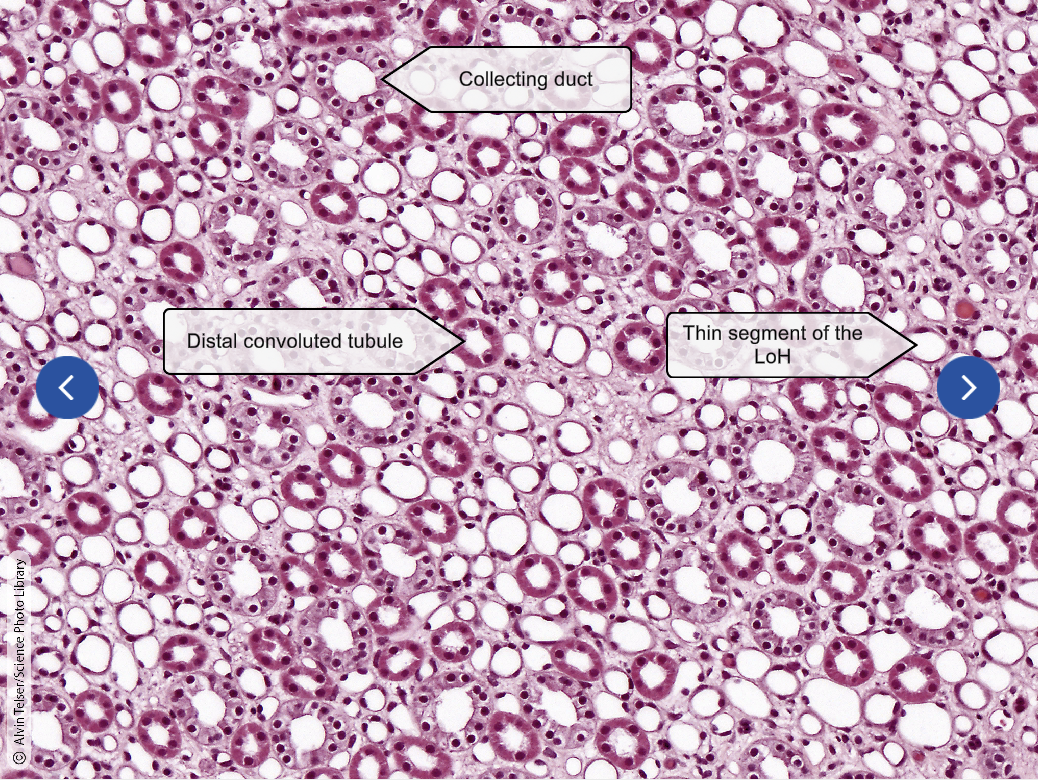

Kidney Medulla

Nephron

Renal Corpuscle

Renal Tubule